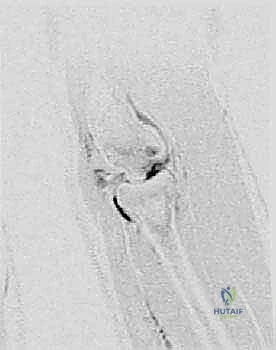

- الأشعة السينية (X-rays):

تُجرى من زوايا متعددة (أمامية خلفية، جانبية، وبزاوية 45 درجة). تكشف الأشعة السينية عن التغيرات في شكل العظم، وجود تسطح في الرأس الصغير، أو وجود أجسام عظمية حرة كبيرة. - التصوير بالرنين المغناطيسي (MRI):